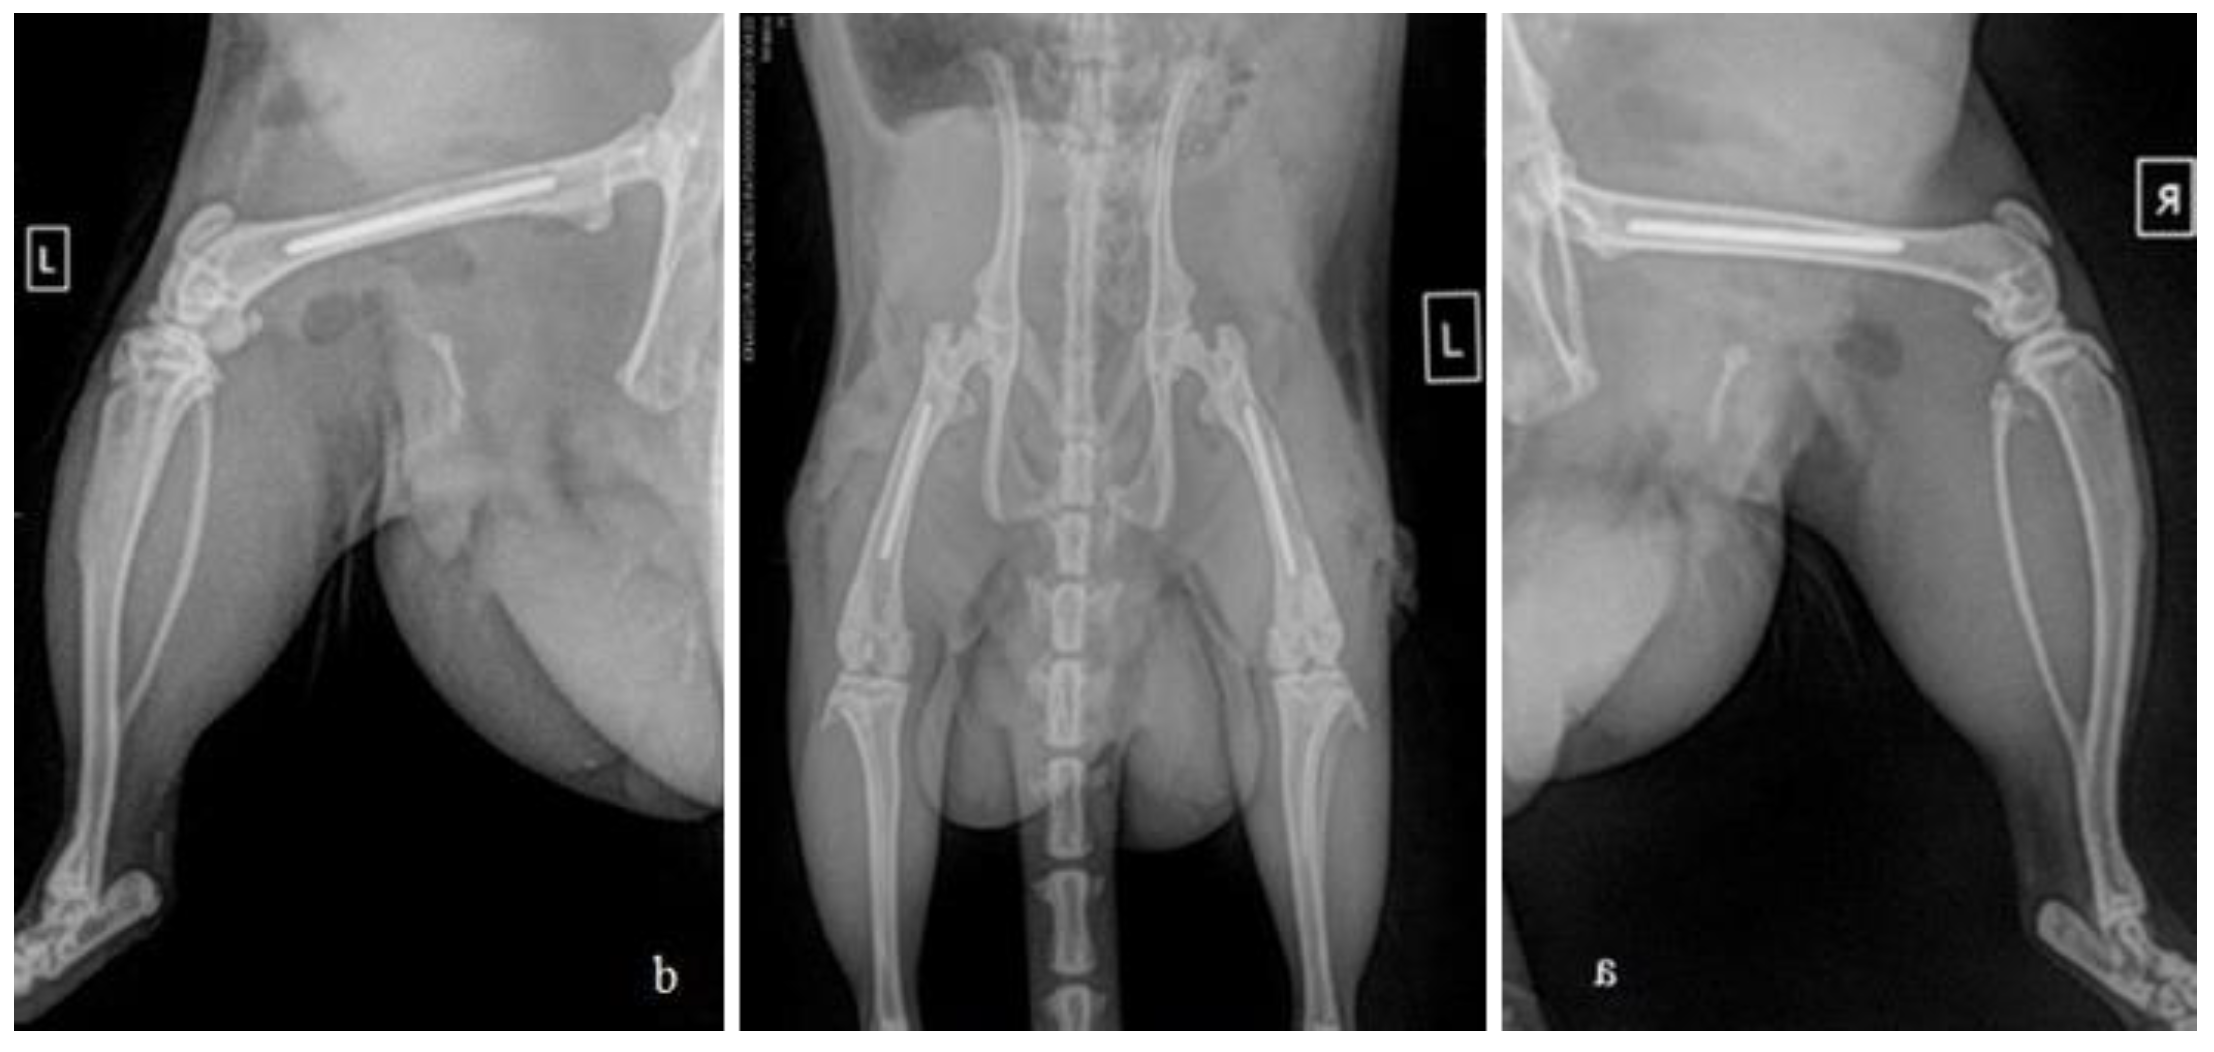

2.3. Surgical procedure and post-operative care

2.4. Post-operative tissue harvesting